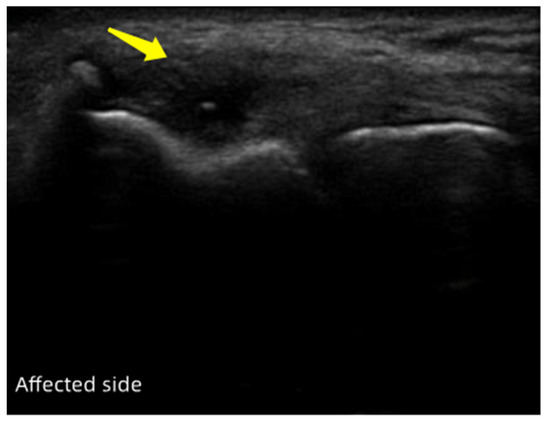

Characteristic of Ultrasonography

3.2. Ultrasonography Evaluation

3.2.1. Case One

3.2.2. Case Two